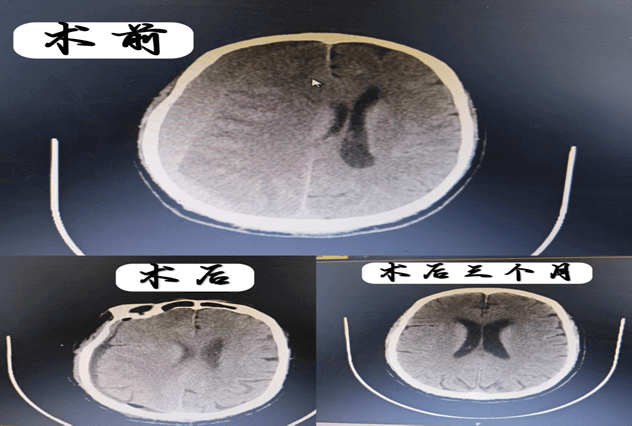

曾经有位75岁高龄的患者,因慢性硬膜下血肿导致头疼头晕,伴有左侧肢体乏力,家属已做最坏打算。经过我们及时的钻孔引流手术,老人第二天神志转清,一周后独立行走出院,三个月后查复硬膜下血肿已基本吸收。这样的奇迹,在我们科室几乎每天都在上演。